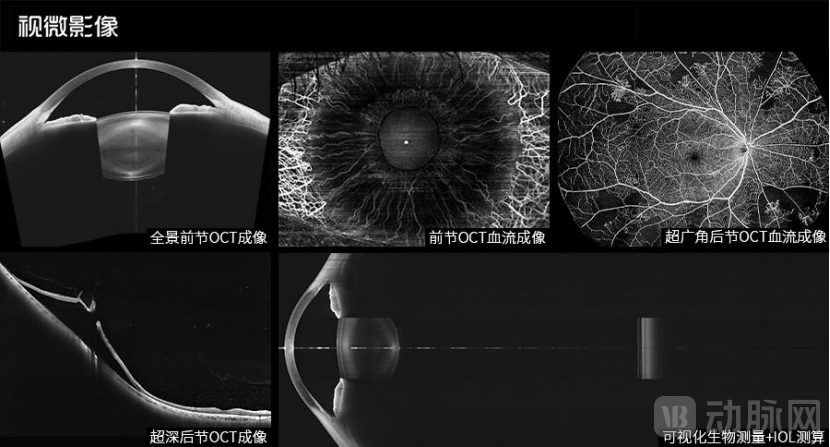

结合临床需求,视微研发团队将最新的扫频技术应用在眼科OCT产品上,同时创新光学系统设计,采用先进AI算法,全球首创了“如意全眼OCT”新技术,成功在同一台设备上整合全眼轴可视化生物测量、前节OCT、后节OCT、前节OCTA、后节OCTA五大功能模块,实现“一机多用”、“一眼全观”,具有重要的里程碑式意义。

1、生物测量功能:生物测量功能是如意全眼OCT近期重磅推出的全新功能模块,这是全球范围内首次将全眼轴可视化生物测量与前后节OCT/OCTA进行整合,在OCT技术发展史上具有里程碑意义。

通过对如意扫频引擎的技术改进,可以实现45mm全眼轴范围的可视化生物测量,包括眼轴长度、角膜曲率、前房深度、晶体厚度,并可在此基础上进行人工晶体度数测算。基于扫频OCT的超强组织穿透力,并结合优化后的系统高灵敏度,可以大幅提升重度白内障患者的眼轴测量成功率和精确度。

如意全眼OCT则能带来高分辨率、高穿透力的极致后节OCT成像,可以穿透重度混浊的晶状体,让眼底情况清晰可见;同时搭载超深成像技术,高度近视患者周边视网膜不反折,从而完整呈现后巩膜葡萄肿的形态;更有超广角扫描技术,一次扫描即可获得26mm超广角OCT图像,不遗漏周边眼底病变。

3、后节OCTA功能:OCTA技术的问世为眼底病诊疗带来了极大便利,但也存在扫描范围偏小、复杂病变分层错乱、无法量化分析等问题。相比传统OCTA产品,如意全眼OCT单次扫描范围可达26mm×21mm(眼内角130°),在此基础上还可实现超过200°自动无缝拼图,临床适应症进一步扩大,进而大幅减少有创造影检查。

此外,如意全眼OCT采用国际先进的“真·血流”算法,结合AI智能分层技术,将对复杂病变和早期微小血管病变表现出更高的检出率,丰富的血流量化工具涵盖了针对血流密度、FAZ、CNV、无灌注区及脉络膜血管指数等参数的测量,可实现对眼底不同层次血流的全方位量化分析。

视微全新的如意全眼OCT搭载如意扫频引擎,突破性地实现了16.2mm超级深度扫描,单次扫描即可完整呈现角膜、前房、虹膜、晶状体甚至前部玻璃体的全景前节高清影像。另外,基于强大的AI算法,可以实现对角膜、房角、ICL拱高等诸多前节数据的自动测量。

5、前节OCTA功能:随着OCT和OCTA影像技术的快速发展,越来越多医生开始尝试通过血流OCT无创观察眼前节血管形态。然而,与眼底OCTA不同,由于虹膜组织内色素含量非常丰富,传统频域OCT因穿透力有限而难以探查到虹膜内的血流信号。

如意全眼OCT基于超强的组织穿透力,更容易透过富含色素的虹膜组织而清晰呈现虹膜血管形态;另外,在超高速扫描和“真·血流”算法的双重保障下,眼前节OCTA成像质量达到了全球领先水平。